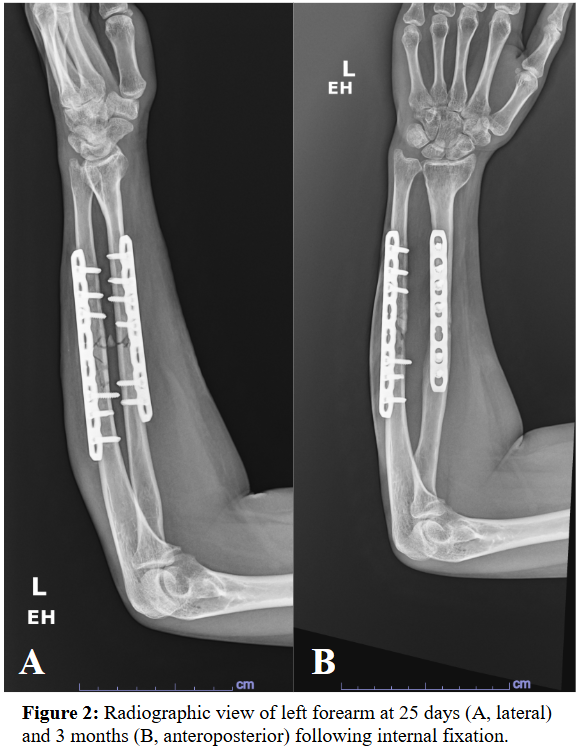

Case Presentation: A 39-year-old female with no past medical history presented 3 weeks after an ATV accident in Lebanon. She had sustained a closed left proximal humerus fracture and an open left midshaft radius/ulna fracture exposed to vegetation. She was treated in Lebanon with urgent open reduction and internal fixation, and irrigation and debridement. Ten days later, she removed her sutures and noted purulent drainage and was treated with 3 weeks of amoxicillin/clavulanate. Upon returning to the US, she was prescribed 1 week of trimethoprim/sulfamethoxazole (TMP-SMX).At initial US follow-up, the forearm had a 1 cm x 1 cm granulating wound without visible infection and mild pain along the ulnar plate with limited hand movement. Radiography confirmed stable fixation. Doxycycline was prescribed for possible deep tissue infection but declined due to GI intolerance.Five days later, she reported persistent bloody drainage. She was evaluated in the ER and scheduled for irrigation and debridement but left against medical advice despite concern for sepsis. Two days later, she returned and underwent irrigation, debridement, and sinus tract excision. Piperacillin-tazobactam and vancomycin were initiated pending cultures.Cultures grew gram-negative rod Buttiauxella izardii/agrestis, determined to be highly susceptible. She completed a 6-week course of ciprofloxacin, followed by 6 months of minocycline suppression due to retained hardware. Infection resolved; however, follow-up shows possible ulnar non-union with persistent pain requiring monitoring.